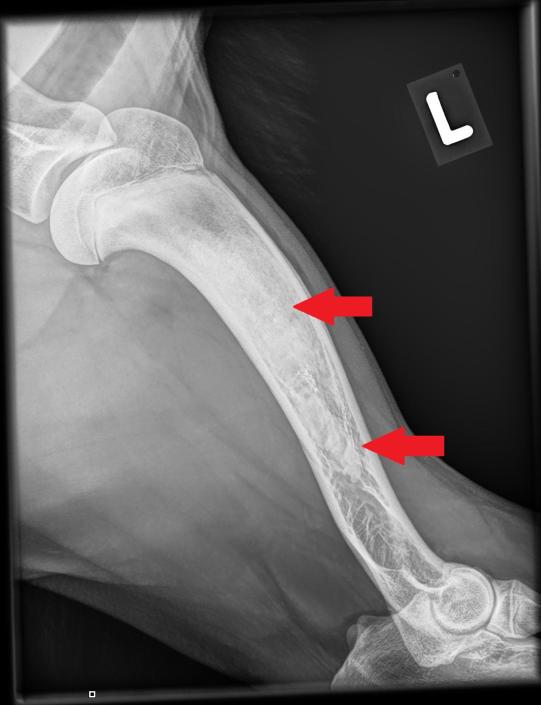

Beim Folgebesuch einige Tage später ist der Hund wieder ganz der alte - ungestüm, fröhlich und mit prächtigem Appetit gesegnet. In Sedation werden nun beide Vorderbeine geröntgt, um zu eruieren, was zu der wechselhaften Lahmheit geführt hatte.

Die typischerweise von Wachstumsstörungen betroffenen Gelenke (Ellbögen und Schultergelenke) erscheinen wie erhofft unauffällig. In sämtlichen Langknochen (Elle, Speiche, Oberarmknochen) beider Vorderbeine zeigen sich jedoch starke Veränderungen: Das Knocheninnere weist an verschiedenen Stellen fleckige Verdichtungen auf, welche die normale feine Knochenstruktur verdrängt haben. Die beobachteten Veränderungen sind typisch für eine sogenannte Panostitis. Die Besitzerin erhält einen Vorrat an Schmerzmitteln, falls das Problem wieder aufflammen sollte.